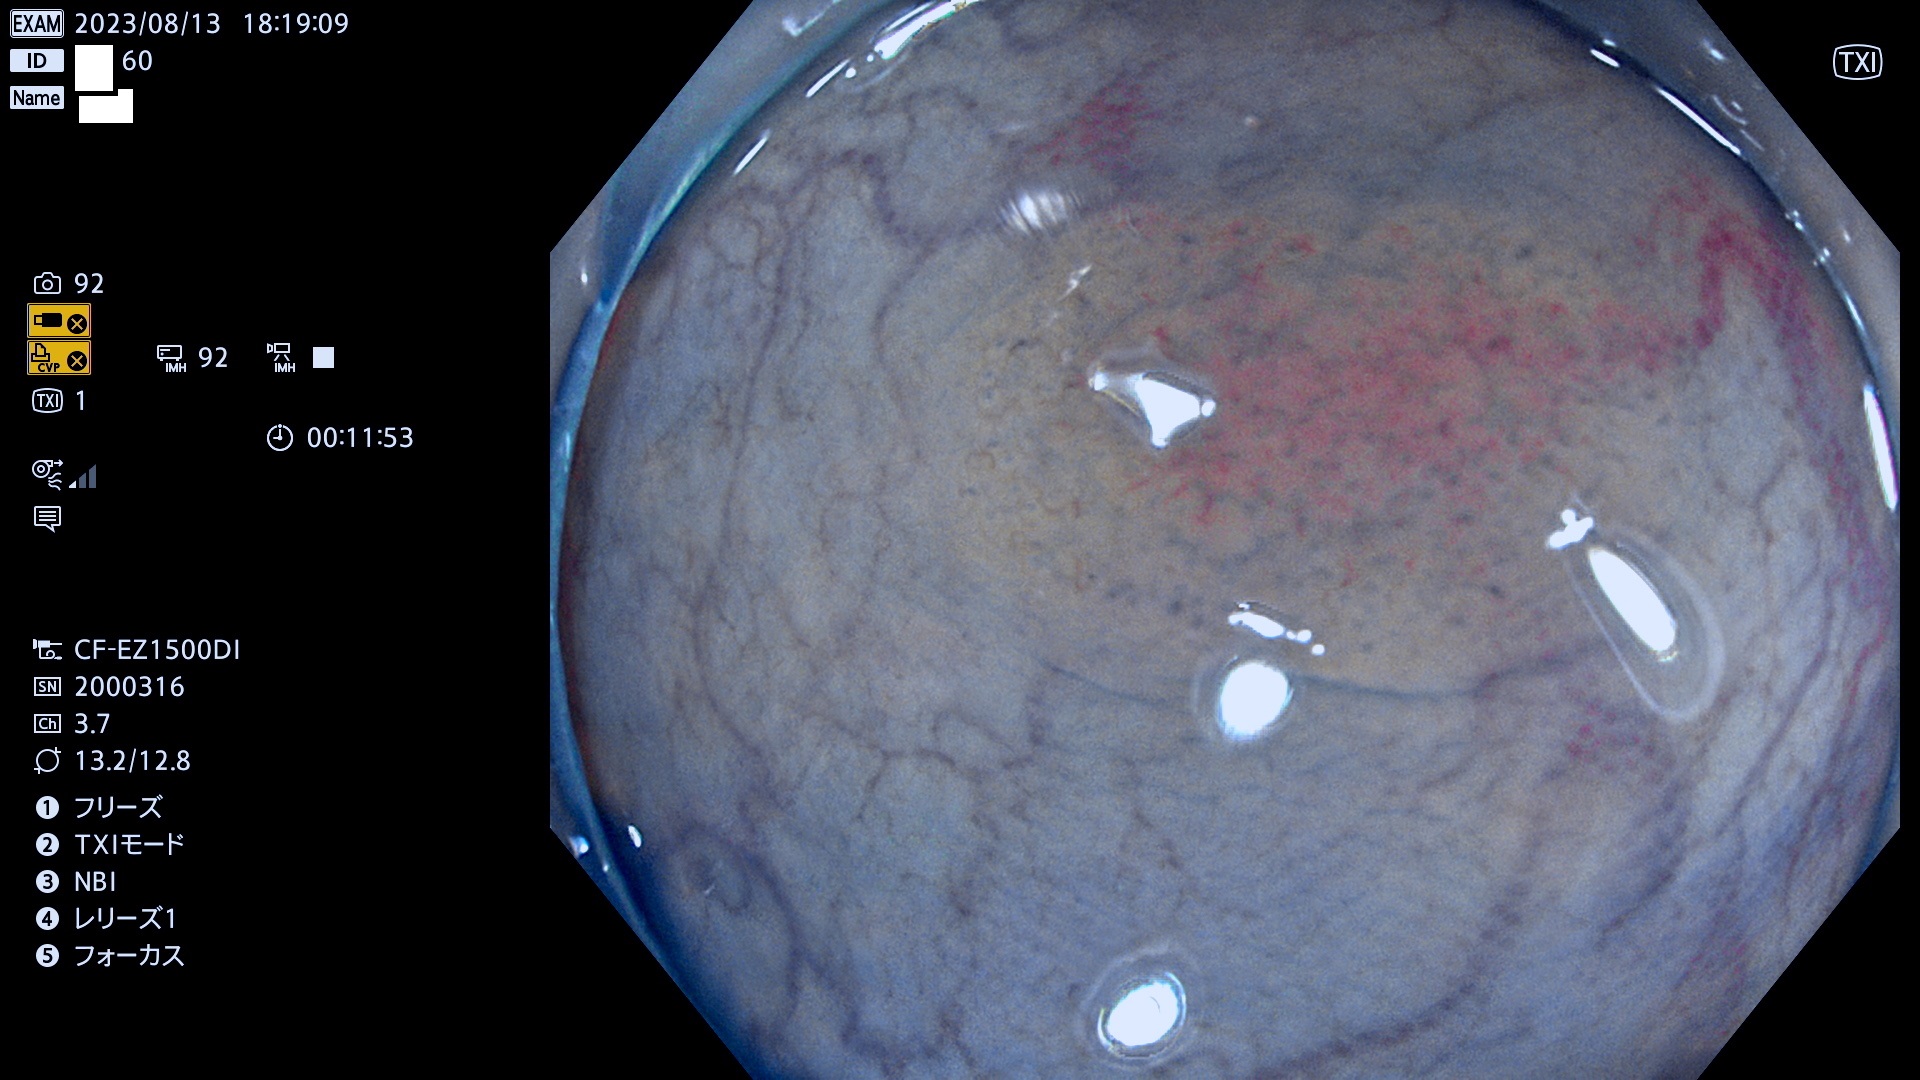

今週のUb、Uc型腺腫

表面型腺腫(Flat Adenoma)の中で、完全に平坦な物をUb、陥凹している物をUcと呼びます。平坦隆起型(Ua)よりも、発見が難しく危険な病変です。このタイプは「内視鏡後・大腸癌の重要犯人」であり、この発見率は「腺腫発見率」よりも、重要な意味があります。

毎週の検査(木・金・土・日)に発見されたUb、Uc型・腺腫を、その週の日曜の夜にUPし1週間、提示します。

抽出の対象期間 2023年8月10日(木)〜8月13(日)の4日間(48件の検査)11件